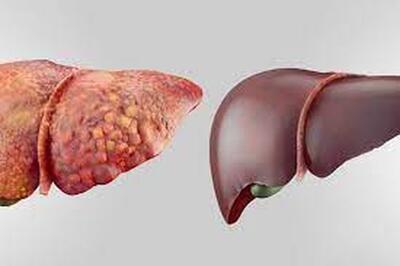

این نوشیدنی کبد شما را نابود و شما را به سمت مرگ میکشاند - سبک ایده آل

فوق تخصص گوارش و کبد با بیان اینکه کبد وظایف بسیاری از جمله مسمومیتزدایی از متابولیتها، ساخت پروتئین و تولید آنزیمهای مورد نیاز برای هضم غذا، را برعهده دارد، گفت:بهترین راهکار مقابله با کبد چرب اصلاح سبک زندگی و انجام فعالیتهای ورزشی است.